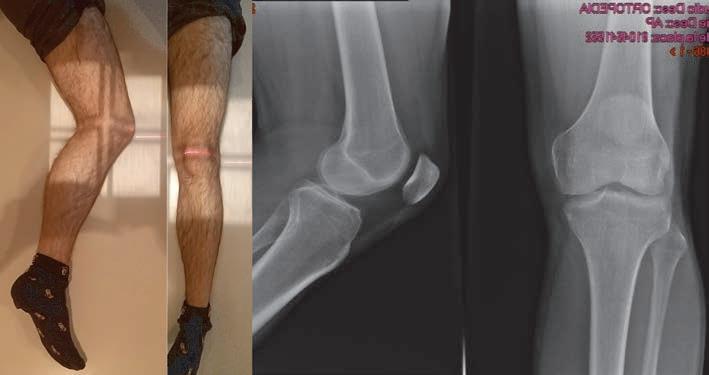

1. Radiografía AP de rodilla. Con esta proyección se evalúan el fémur distal, la tibia proximal, el peroné proximal, la posición y anatomía de la rótula, posibles fracturas intraarticulares y la simetría de los espacios articulares femorotibiales. Técnica: paciente en decúbito supino o sentado en la mesa, con la pierna extendida y el chasis en la región poplítea. El rayo entra perpendicular al chasis, 1,25 cm distal al polo inferior de la patela.

Puede requerirse en pacientes de contextura muy delgada inclinar el rayo de 3°-5° caudal para que sea paralelo a la superficie articular de los platillos tibiales. En pacientes con obesidad puede requerirse inclinar el rayo de 3° a 5° cefálico para que el rayo sea paralelo a la superficie articular de los platillos tibiales (23) (figura 20). 2. Radiografía lateral de rodilla. En esta radiografía se evidencia la tibia proximal articulada con el fémur distal. Sirve para descartar luxaciones

de rodilla y su dirección. Se encuentra la rótula en vista lateral y muchas veces es más fácil diagnosticar fracturas de rótula en esta proyección. La radiografía lateral permite evaluar fracturas y el desplazamiento anteroposterior de los fragmentos alrededor de la rodilla. Técnica: paciente en decúbito lateral del lado que se va a examinar contra la mesa. Con una ligera flexión de 20°-30° de la rodilla. La extremidad contralateral debe realizar extensión de la cadera para evitar sobreponer la imagen. El rayo entra con 5°-7° de inclinación cefálica, centrado a 2,5 cm distal del epicóndilo medial. Los cóndilos femorales deben verse superpuestos y para lograrlo pueden requerir apoyo bajo el tobillo y el pie afectados para lograr la rotación necesaria (23) (figura 20).

Figura 20. Radiografía anteroposterior y lateral de rodilla

Fuente: elaboración propia